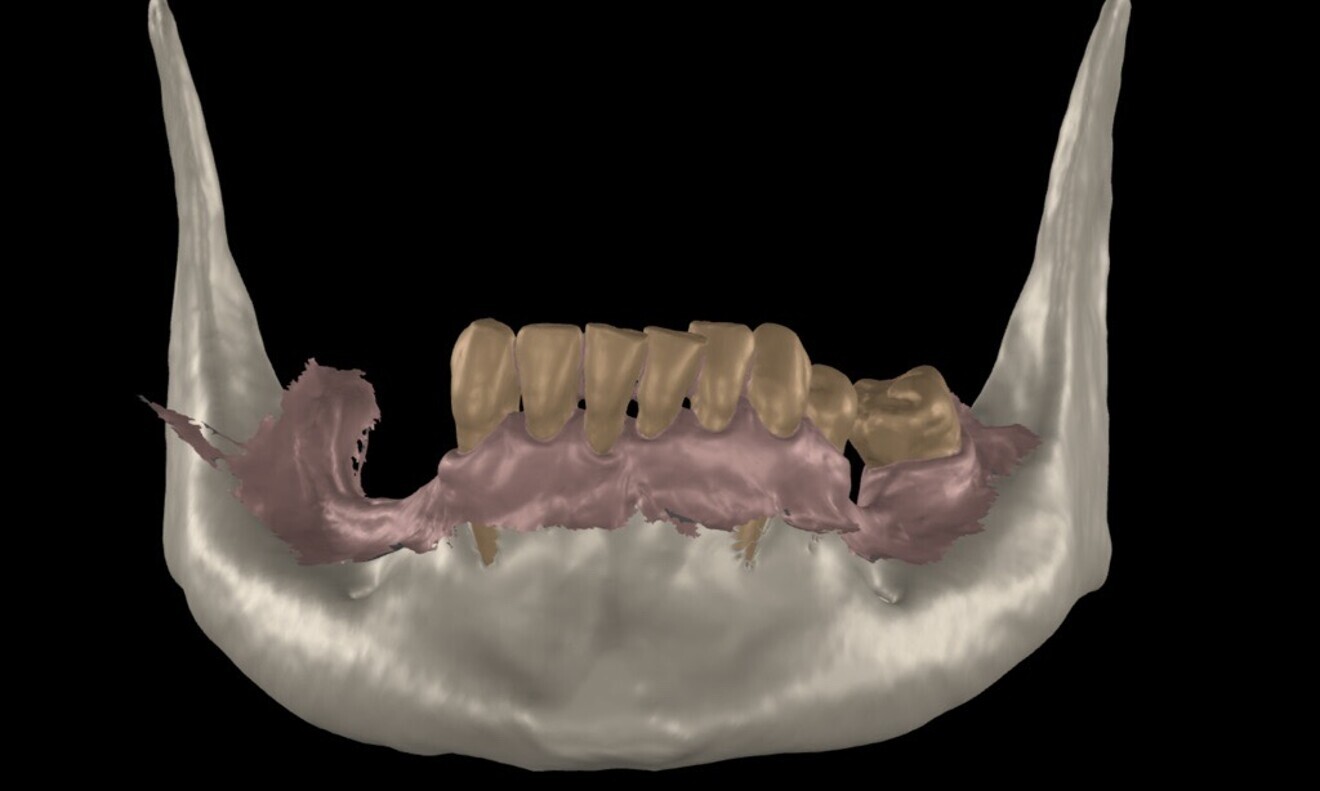

To ensure precise and predictable treatment planning, the DICOM files, STL files and clinical photographs were seamlessly integrated into Smilecloud, utilising advanced artificial intelligence technologies to deliver a highly personalised smile with exceptional precision (Figs. 11–15).

Figs. 11–15: DICOM files, STL files and clinical photographs were integrated into Smilecloud, leveraging artificial intelligence for precise, personalised smile design.